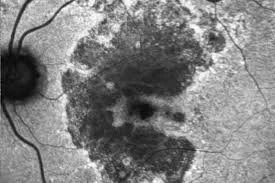

Fundus auto fluorescence image showing geographic atrophy. The darker areas represent non functional retinal cells and retinal thinning.

Fundus auto-fluorescence demonstrating geographic atrophy (black areas)